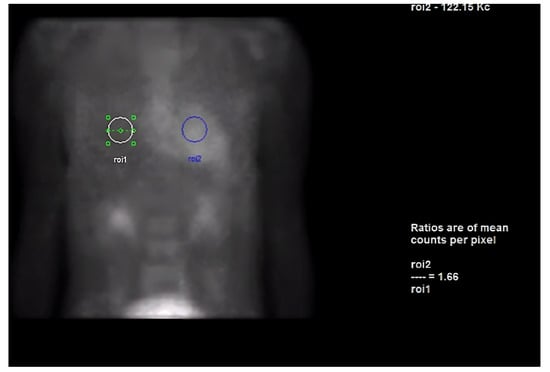

Next, we performed a 99Technetium pyrophosphate (99mTc-PYP) planar scintigraphy (Figure 4). A quantitative analysis of the heart retention pattern showed a heart-to-contralateral lung (H/Cl) ratio of 1.66 (Figure 5), strongly suggestive of amyloid deposition. To differentiate the type of cardiac amyloidosis, genetic testing was obtained and revealed a heterozygous pathogenic mutation in the TTR gene, diagnostic for TTR amyloidosis.

Figure 5. Heart-to-contralateral ratio was calculated by drawing a region of interest over the heart, mirroring it to the contralateral chest, and calculating the ratio of heart ROI to contralateral chest ROI mean counts. The representative image demonstrates a H/CL ratio of 1.6. (H/CL, heart-to-contralateral; ROI, region of interest).